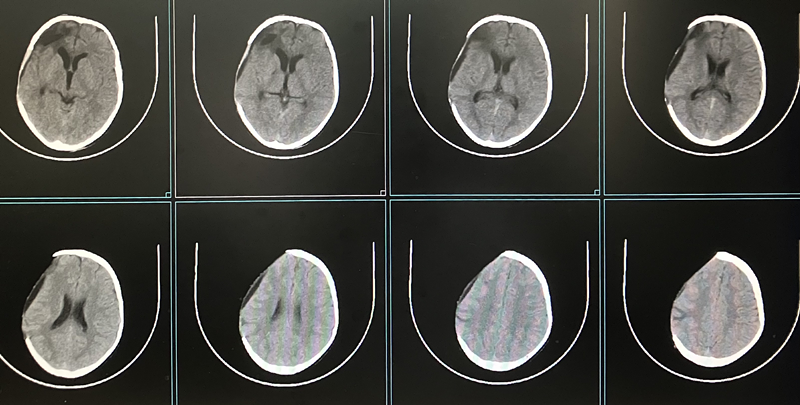

术前头颅CT

经过充分术前检查、讨论,并制定周密的手术方案。由池超超副主任医师主刀,周元鼓副主任医师配合进行手术,术中池超超副主任医师取三维塑形PEEK板置于骨窗,精准嵌合满意后,以颅骨锁、PEEK片、钛钉固定良好,手术顺利完成。